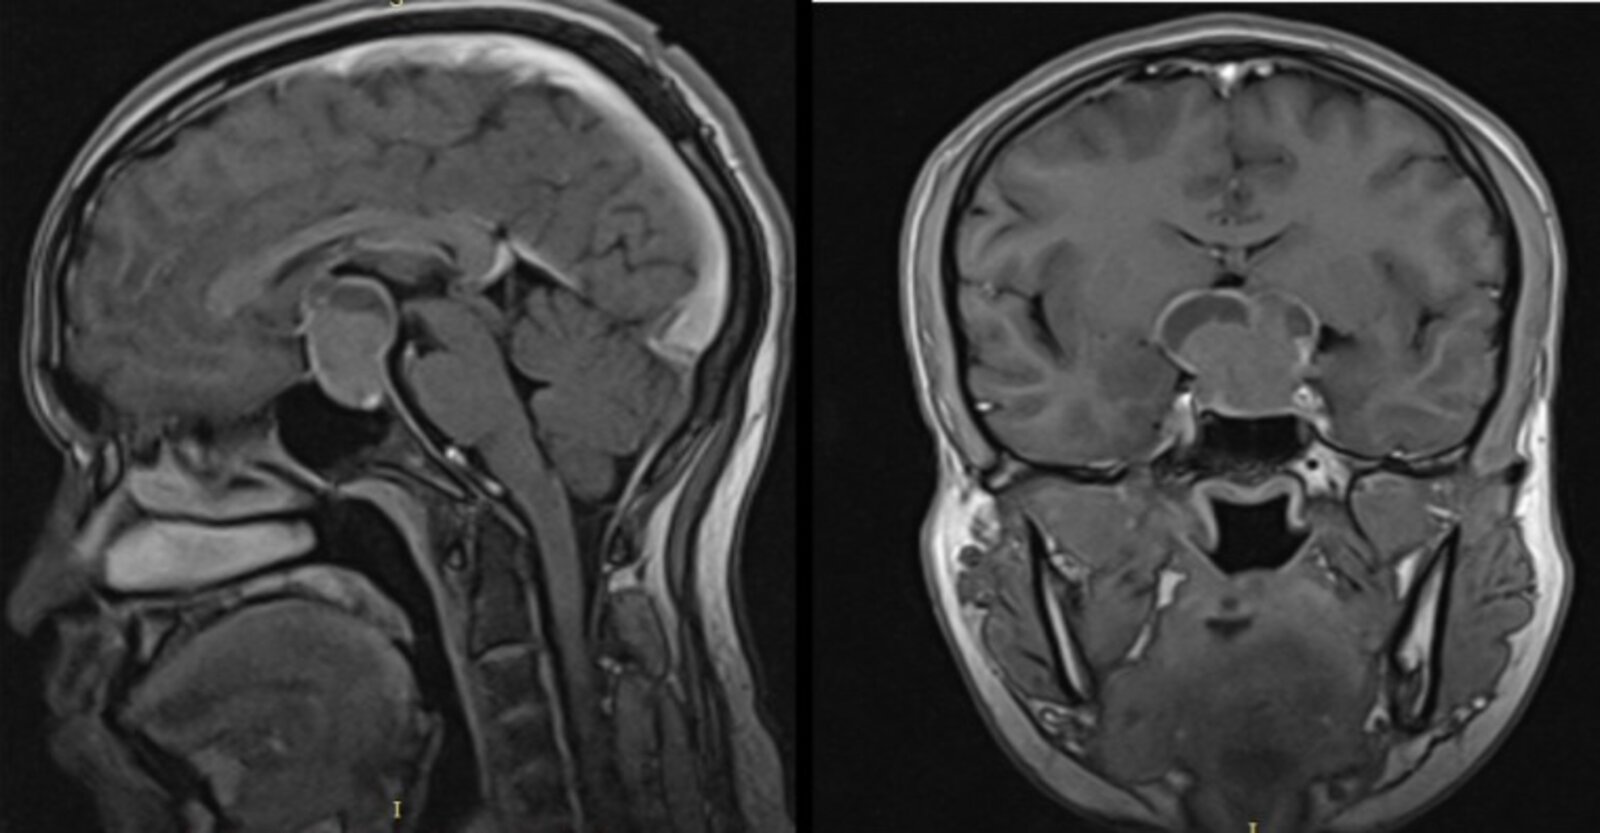

Imaging [12]

Imaging of the pituitary is indicated in all patients to determine the underlying cause.

• MRI brain

• Preferred imaging modality

• Findings depend on the underlying etiology and include pituitary adenomas (most common cause in adults), congenital malformations, and trauma.

• CT Head (without IV contrast): used if there are contraindications to MRI or in patients requiring rapid evaluation, e.g., after suspected TBI or SAH